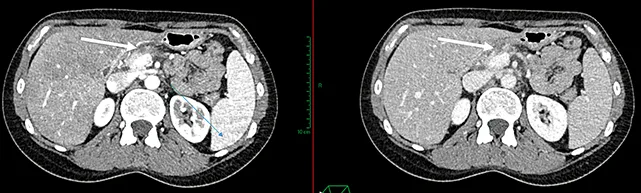

Figure 2 : AP isthmique, résécable d’emblée selon la définition du NCCN, présentant un contact veineux < 180°

Figure 3 : AP borderline artériel. Envahissement veineux (VMS) < 180° et artériel (AMS) < 180°